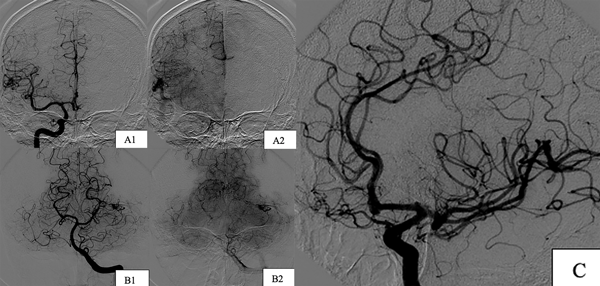

Paciente de sexo femenino, de 17 años, sin antecedentes patológicos, a quien en contexto de estudio por episodio de crisis comiciales de novo se le diagnostican dos MAVs supratentoriales, una frontal derecha de 25 x 29 mm diámetro, con aferencias silvianas, de nido compacto y drenaje hacia el seno longitudinal superior a través de gran vena cortical y otra temporal izquierda de 16 x 11 mm con aferencias silvianas, de nido compacto y drenaje hacia el seno transverso, sin evidencia de signos sugestivos de sangrado (Figura 4). Se decidió estudiar y descartar síndromes congénitos para luego programar la cirugía. Debido a que ninguna de las dos lesiones presentaba factores angiográficos de rotura y por su localización en el hemisferio no dominante se decidió abordar inicialmente la malformación frontal derecha (Figura 5) y 7 meses después se realizó la exéresis de la restante con control angiográfico postquirúrgico satisfactorio y ninguna complicación asociada (Figura 6).

Figura 4. Imágenes preoperatorias caso 2. A) MAV frontal derecha. A1) Incidencia frente. A2) Incidencia perfil. A3) Incidencia axial de RM. B) MAV temporal izquierda. B1) Incidencia frente. B2) Incidencia perfil. B3) Incidencia axial RM.

Figura 6. Imágenes postoperatorias caso 2. Incidencias derechas. A1) Corte coronal. A2) Corte sagital. B) Incidencias izquierdas. B1) Corte coronal. B2) Corte sagital.